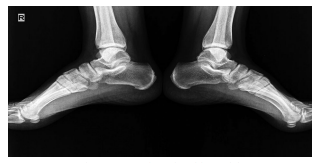

Enthesopathy is a reported side effect of isotretinoin and usually develops after long-term isotretinoin use.[37,38] However, cases associated with short-term isotretinoin treatment have also been reported in the literature. Tendinitis of the Achilles tendon is a known side effect of isotretinoin and has been reported in 9.5% of patients.4 A close relationship between Achilles tendinitis and isotretinoin dose has also been described.[39,40] In our study, the patient who developed tendinitis was on low-dose isotretinoin treatment. Dose reduction and interruption can be considered in patients developing tendinitis.[39] The symptoms of the patient in the current study regressed with the cessation of treatment.